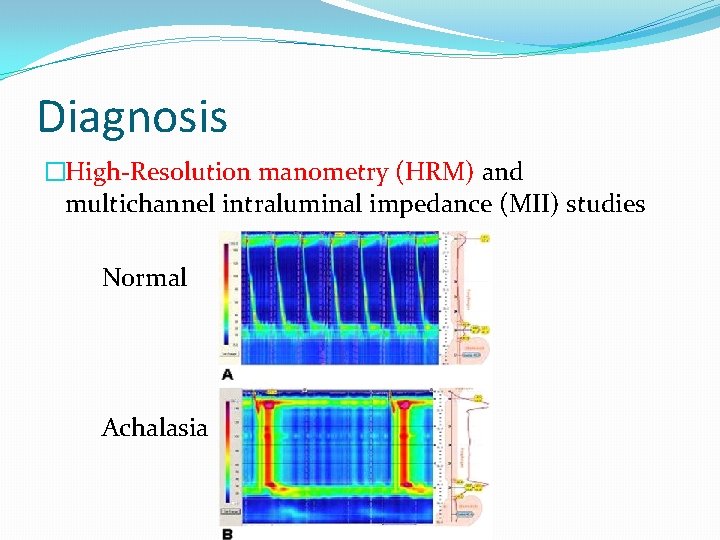

Diagnosis �The gold standard for diagnosis of achalasia is esophageal manometry. �Manometry is especially helpful in early disease state when other diagnostic evaluations appear normal.

Diagnosis �Residual LES relaxation pressure to be the most accurate diagnostic manometric criteria. �A residual pressure of >12 mm. Hg had 92% sensitivity. � Aperistalsis, a residual pressure of >10 mm. Hg had 100% sensitivity and 100% positive predictive value.

Diagnosis �High-Resolution manometry (HRM) and multichannel intraluminal impedance (MII) studies Normal Achalasia